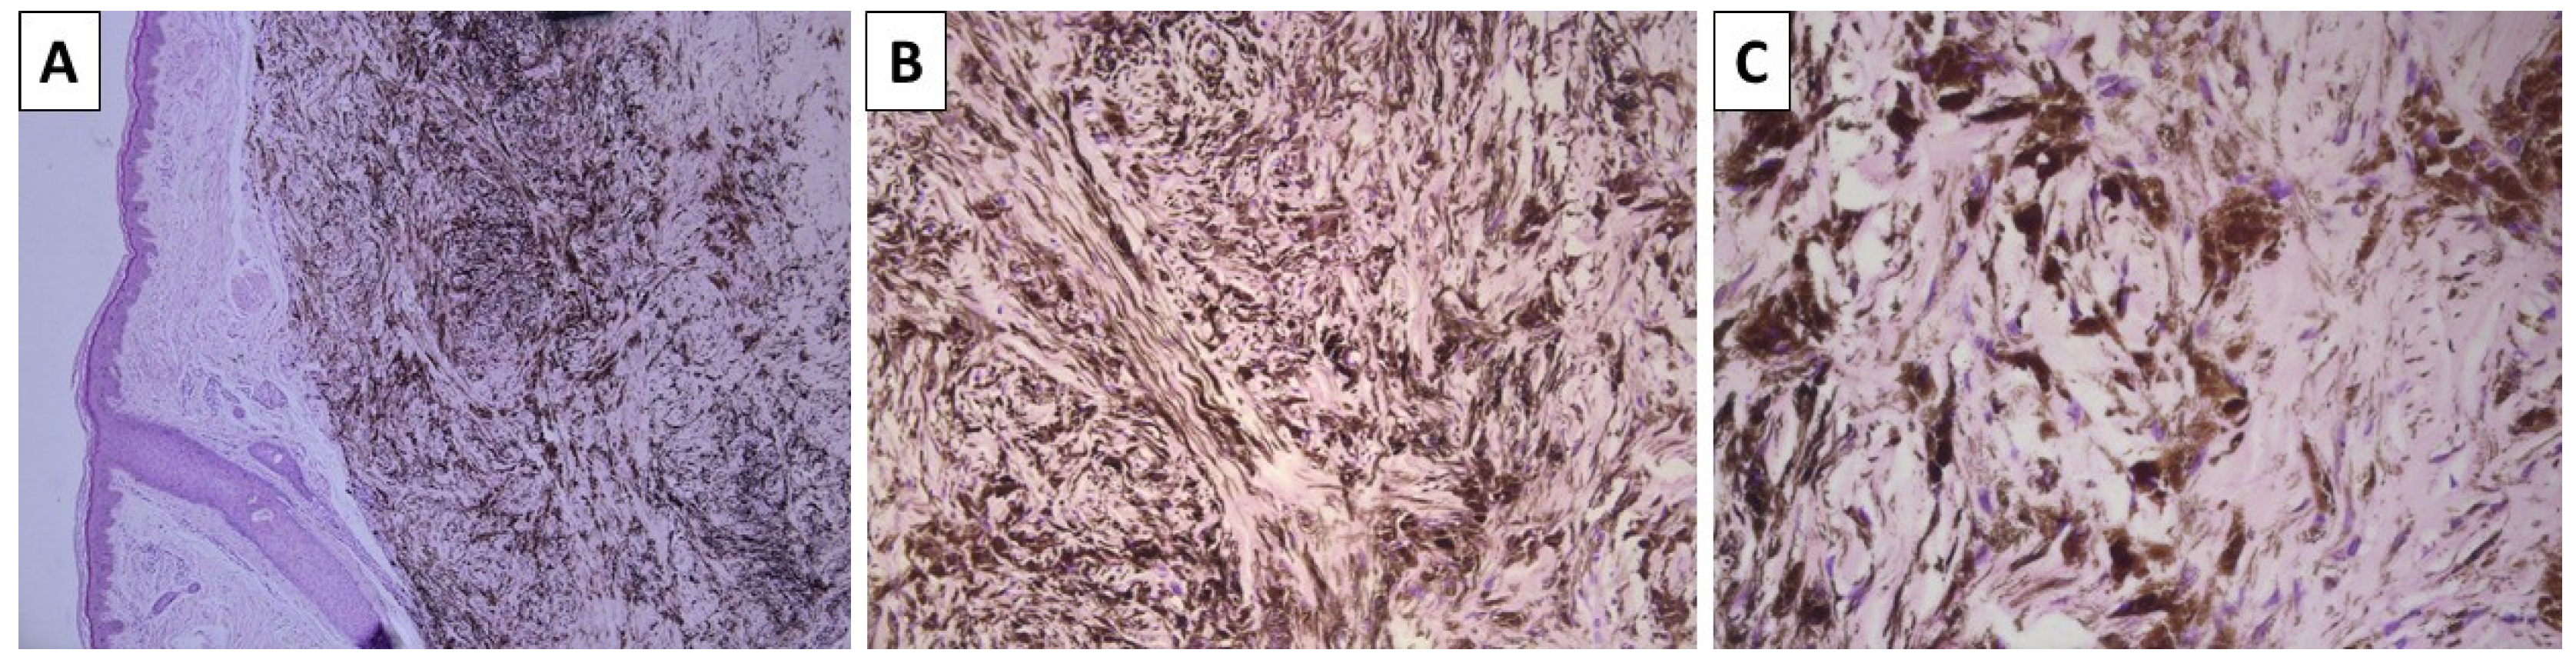

A previously healthy 43-year-old female presented to outpatient dermatology consultation due to two pigmented lesions on the dorsal side of the left wrist. The patient could not specify the exact time for which the lesions had been present but stated that they had been present for at least 10 calendar years. The first lesion was topographically located above the first metacarpal bone, was dome-shaped with a blue hue, and measured 6 × 4 mm. The lesion was sharply demarcated with smooth borders. The second lesion was topographically located above the second metacarpal bone, had nearly identical characteristics, and measured 15 mm in diameter. Due to the size of the first depicted lesion and the desire of the patient for its removal, surgical excision was performed. The specimen sent for pathology was represented by a leaf-like skin specimen, measuring 10 × 8 mm, with a centrally placed pigmented lesion of a black-blue color, sharp edges, and a gross distance from the resection margins of 1 mm. On cross-section, the lesion was dermally located and did not involve the deep reepithelial margin. Histology sections revealed non-involved resection margins and a deeply located dendritic melanocyte lesion in the dermis, with significantly colagened stroma and extensive intracellular pigment deposition to the point of nucleus masking (Figure 1). Hence, the diagnosis of dermal blue nevus was established.

Figure 1.

Histopathology of the lesion. (A) dermally based pigmented lesion, original magnification 40×; (B) spindle-cell and dendritic melanocytes with intense pigment deposition, original magnification 100×; (C) dendritic melanocytes are admixed with sclerotic stroma, original magnification 200×; staining (A–C) hematoxylin and eosin.